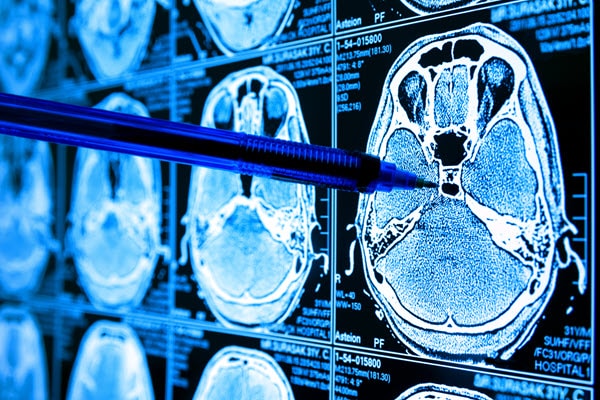

(Source: zapp2photo - stock.adobe.com)

Scientists have used many ways of testing and looking at cancer over the years, but microscopy and other imaging techniques have been some of the key methods. The days are gone when a scientist would look under the microscope and come to a conclusion without any computer assistance. In recent years, a number of computer software programs enabled scientists to look at the shape, size, and morphology of imaging samples, including cells. However, many of these programs still require human input to characterize where the points of interest, in this case, the cancer cells, start and where they stop. These imaging methods have been designed for a range of analysis equipment, from the simple lab bench microscope to MRI scanners.